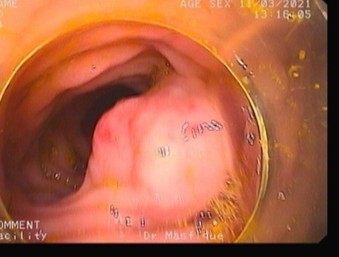

Refer to caption

Figure 1: Examples of colorectal polyp morphologies observed during colonoscopy. (a) Sessile polyp lying flat against the colonic mucosa, making detection more challenging.(b, c) Pedunculated polyps with stalk-like structures protruding from the mucosal surface.

Colorectal polyps generally exhibit two distinct morphologies: sessile (flat) and pedunculated (stalked) as shown in Fig.1. Sessile polyps, which are now recognized as more prevalent than once believed, are particularly challenging to detect during colorectal cancer screening due to their flat structure that closely adheres to the mucosal surface of the colon. In contrast, pedunculated polyps resemble a mushroom-like structure, protruding from the mucosal lining and connected by a narrow, elongated stalk [13] .